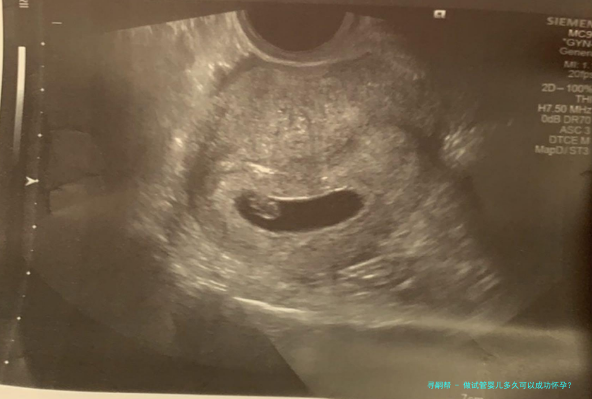

七、确定怀孕